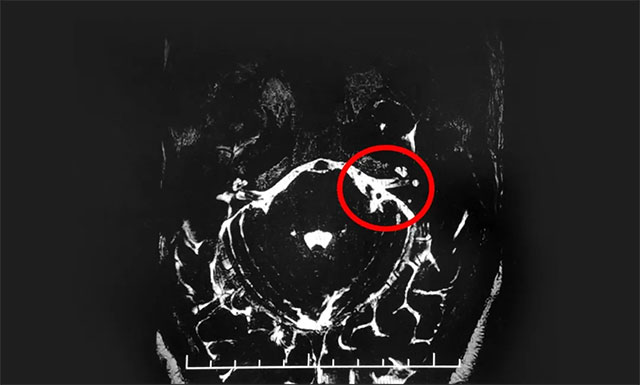

▲ 影像显示,患者双侧三叉神经与周围小血管关系密切(左侧为著)

在办理入院手续后,杨忠旭教授详细了解了老刘的病史资料,并为其申请了三叉神经MRTA平扫+增强等相关检查。结合影像资料,杨忠旭教授指出患者双侧三叉神经与周围小血管关系密切(左侧为著),手术指征明显,未见明显手术禁忌症。